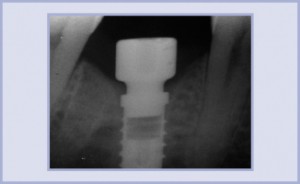

La tecnica chirurgica monofase, qualora possibile, permette una minore perdita ossea complessiva a livello coronale; negli impianti Exacone® si evidenzia a volte, addirittura, una certa crescita ossea intorno al collo della fixture, come in questo caso (figg. 9-11). Vista la qualità di osso rilevata in fase chirurgica abbiamo preferito aspettare 6 mesi prima di protesizzare l’impianto. Dopo aver preso l’impronta (figg. 12-14), abbiamo preparato il moncone in laboratorio, verificandone poi la congruità in bocca (figg. 15-21).

- Fig. 10 – Immagine radiografica a 3 mesi dalla chirurgia

- Fig. 11 – Immagine radiografica a 6 mesi dalla chirurgia